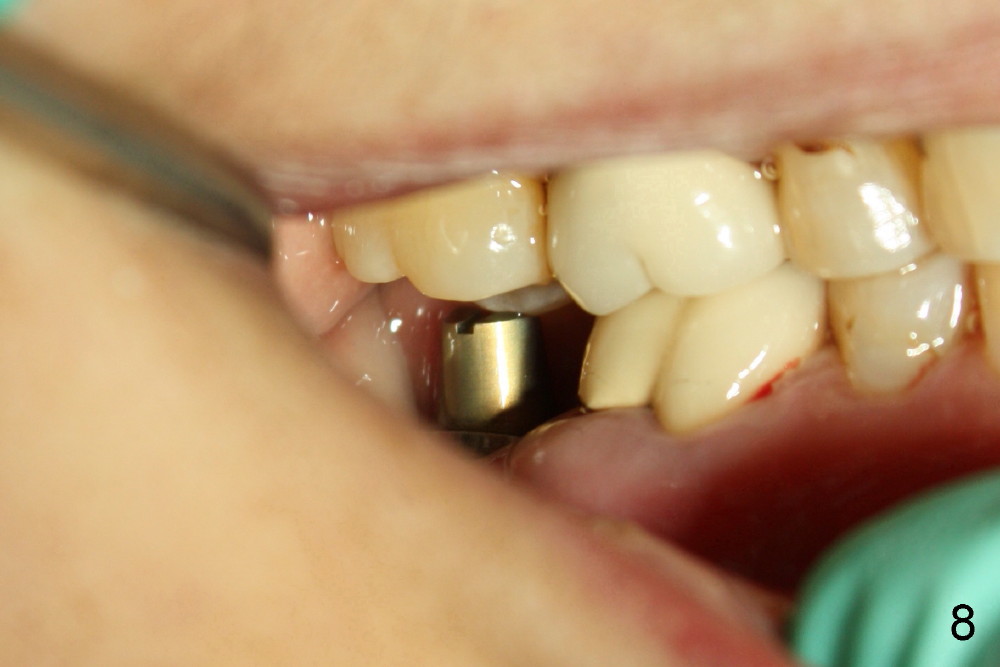

When a 4.5 mm 20 degree short unipost is engaged into the implant, it touches the opposing tooth (Fig.8). The unipost has to be cut (Fig.9). It takes at least 5 minutes to finish. Finally there is enough clearance for crown (Fig.10). This is my first experience to cut the unipost. The good thing is that I learn the shortened unipost does not seem to affect retention of crown.